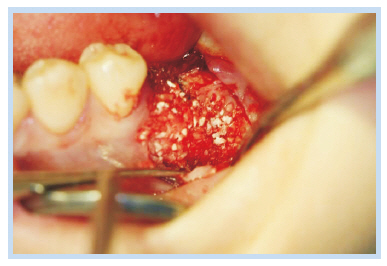

22세 여성이 하악 좌측 제1대구치 임플란트 부위의 저작 시 동통을 주소로 내원하였다. 5개월 전부터 하악 제1대구치 임플란트 부위의 저작 시 동통을 느꼈으며, 가만히 있을 때는 동통이 없다고 하였다. 치근단 방사선 사진에서 골 유착이 파괴된 양상을 보였고 원심 측에 방사선 불투과상을 보이는 잔존 치근으로 추정되는 것이 관찰되었다(Fig. 6). 하악 제1대구치의 임플란트 동요도가 심하여 국소마취하에 fixture를 제거하였고(Fig. 7), 원심 측의 잔존 치근은 그대로 남겨둔 채로 임플란트 식립을 계획하였다. 치조정 절개 및 골 점막 피판을 거상하여 직경 6 mm 높이 12 mm의 임플란트(Dentium Superline; Dentium, Seoul, Korea)를 식립하였다(Fig. 8). 임플란트의 근심측과 협측에 6 mm 높이의 열개가 존재하여 동종골(PEDI-STICK) 이식을 시행하였다(Fig. 9). 덮개 나사를 연결한 후 피판을 재위치시키고 4-0 Vicryl로 봉합하였다. 2주 후 봉합사를 제거하였고 치근단 방사선 사진을 촬영하였다(Fig. 10). 술 후 2개월에 2차 수술을 시행하면서 치유 지대주를 연결하였고(Fig. 11), 술 후 4개월에 최종 보철물을 장착하였다. 임플란트 식립 12개월 후 치근단 방사선 사진을 통해 안정적으로 임플란트가 유지되고 있음을 관찰할 수 있었다(Fig. 12).

Fig. 9. Bone graft was performed.